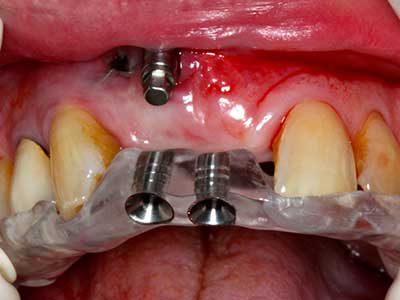

En la extracción de bloques óseos la piezocirugía también presenta ventajas adicionales: Además de la alta precisión en la osteotomía que ya se ha descrito antes, se ha comprobado que el uso de los delgados insertos de sierra resulta especialmente cuidadosas con el hueso. Frente a esto, sobre todo cuando se usan las fresas de Lindemann, cabe esperar pérdidas en la extracción significativamente más altas debido al mayor grosor de la parte frontal del cabezal (Lakshmiganthan, Gokulanathan et al. 2012). La separación basal que se necesita en particular en los injertos de bloque extraídos de forma retromolar se ve facilitada mediante sierras perpendiculares especialmente previstas a tal fin, lo que permite considerar que la cirugía piezoeléctrica es un procedimiento preciso y seguro para la obtención de bloques de hueso en el área retromolar (Happe 2007) (fig. 1-12).

El tejido óseo no solo tiene un contenido puramente mineral, sino que también presenta una importante proporción de fibras de colágeno. Esto no solo garantiza una buena resistencia a la presión, sino también una cierta flexibilidad, que puede aprovecharse para la realización de aumentos. En la plastia de expansión clásica a efectos de una partición ósea, la cresta maxilar atrofiada se divide en su eje longitudinal y, tras alcanzar una profundidad de osteotomía suficiente, se extiende con cuidado (fig. 13-16), en un caso ideal sin desperiostizar de forma visible el maxilar (Brugnami, Caiazzo et al. 2014, Stricker, Fleiner et al. 2014). Los sistemas de tornillos y placas con distancia de expansión creciente han demostrado su eficacia para distanciar entre sí las dos tablas óseas por debajo del umbral de rotura. Por regla general, se requieren anchuras de hueso residual de al menos 3 a 4 mm (Chiapasco, Zaniboni et al. 2006) para garantizar una flexibilidad y una cobertura ósea suficientes de los implantes que van a incorporarse. En caso necesario, una osteotomía de descarga vertical unilateral o bilateral puede mejorar la flexibilidad. Como alternativa a la técnica clásica se ha descrito una combinación con otras técnicas de aumento, sobre todo en la parte bucal.

Con el uso de sierras piezoeléctricas la división se efectúa de forma especialmente cuidadosa y sin pérdidas importantes de las dimensiones, por lo que no se han encontrado diferencias significativas entre los implantes realizados en el maxilar dividido y en la cresta alveolar no deficitaria (Chiapasco, Zaniboni et al. 2006, Danza, Guidi et al. 2009). No obstante, precisamente en la partición profunda y limitada de forma local, es preciso asegurarse de que exista una adecuada irrigación por agua para evitar que se produzcan sobrecargas térmicas en las áreas de osteotomía apical.